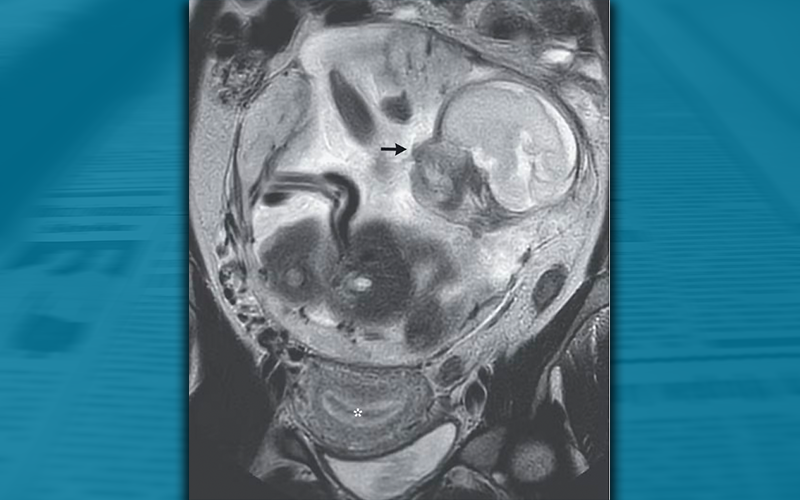

Apesar de ter um bebê de 23 semanas dentro do corpo, o útero da mulher estava completamente vazio. O feto havia se fixado na membrana que reveste a cavidade abdominal, logo acima do cóccix da mãe: um diagnóstico raro de gravidez abdominal. Devido ao alto risco de hemorragia materna e óbito fetal, a paciente foi transferida para um hospital de cuidados terciários.

Para a mulher, a visita oportuna ao pronto-socorro salvou sua vida. Uma ultrassonografia e uma ressonância magnética mostraram que, embora o revestimento do útero estivesse totalmente preparado para apoiar um embrião em crescimento, com o endométrio espesso, ninguém estava lá.